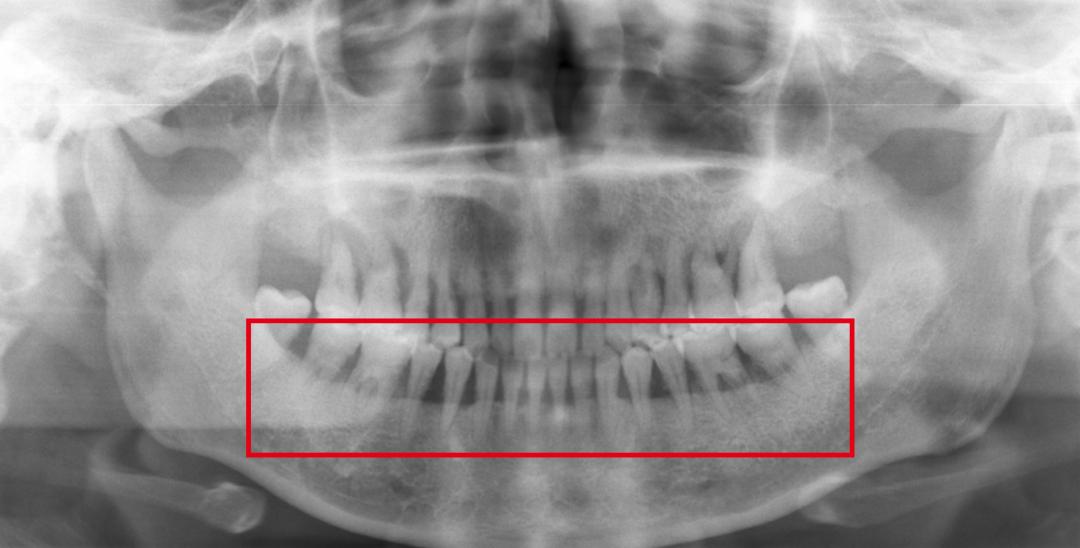

牙龈出血如果不及时治疗,刺激因素持续存在,牙龈下方的牙槽骨就会逐渐被破坏吸收,牙龈出现萎缩,牙齿失去支持,慢慢松动甚至脱落。

如果把牙齿比作大树,牙槽骨和牙龈就像包裹树根的泥土,土越来越少,树根暴露越来越多,最终树倒。

X线片显示牙龈退缩和牙槽骨丧失